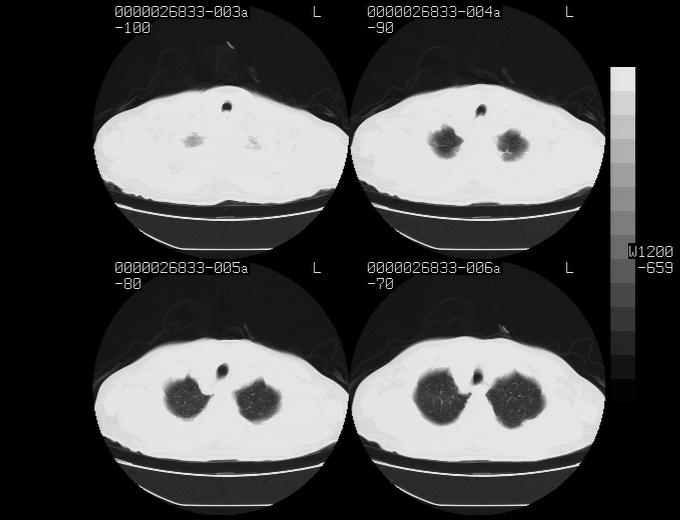

女性,77岁,胸部疼痛半月。左上肺团块影,本人考虑血管畸形,请分析

非常典型的avm(谢谢楼主,收藏了)

1、考虑avm可能性大。2、纵隔有肿大淋巴结,左肺上叶有炎性病变,不排除肺癌并转移可能。